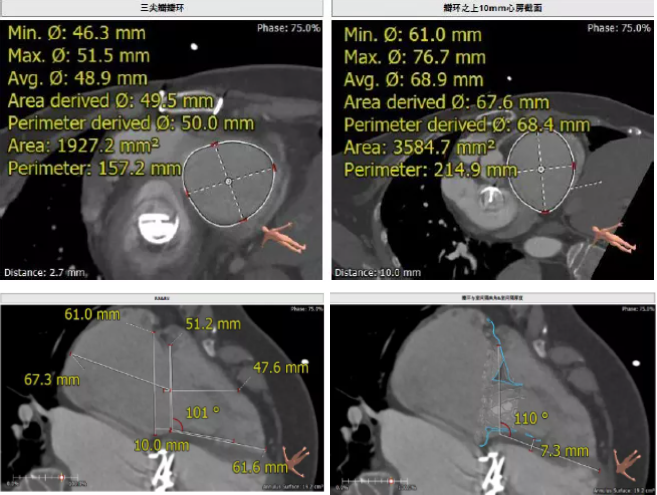

患者為68歲女性,14年前因“反復(fù)感冒、氣促”,檢查發(fā)現(xiàn)心臟瓣膜病,接受了“二尖瓣機(jī)械瓣置換術(shù)”。約5年前出現(xiàn)雙下肢水腫,活動后心累氣緊,心臟彩超提示:三尖瓣返流。近年來三尖瓣返流逐漸加重并伴有輕微黃疸、雙下肢水腫,雖長期服用利尿劑治療,但效果欠佳。郭惠明教授團(tuán)隊結(jié)合病史、超聲及CT評估,考慮患者瓣膜置換術(shù)后,三尖瓣重度返流,再次開胸行體外循環(huán)手術(shù)風(fēng)險高,經(jīng)團(tuán)隊整體評估,決定采用最適合患者的LuX-Valve三尖瓣置換系統(tǒng)行微創(chuàng)治療,根據(jù)測量結(jié)果選擇植入JS/TTVI-28-55型號的LuX-Valve瓣膜。